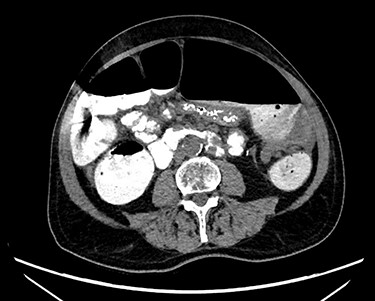

Abdominal X-ray revealed a grossly distended loop of colon with air-fluid levels, consistent with a large bowel obstruction (Fig. 1). A computed tomography (CT) scan demonstrated two transition points in the left colon with swirling of the mesentery, indicative of volvulus (Fig. 2). Following successful endoscopic decompression, the patient proceeded to laparoscopy and colopexy. The previous laparoscopic port sites were utilized. On table colonoscopy was performed during laparoscopy to allow delineation and decompression of the volvulus. As seen in Fig. 3A, the neo-left colon travelled behind the transverse colon mesentery and formed an alpha-type loop. Adhesions fusing the transverse colon mesentery to the neo-left colon were divided to mobilize the colon and to assist in devolving the bowel (Video 1). Interrupted polypropylene sutures were then used to fix the neo-left colon to the posterior gastric wall (Fig. 3B) and the left lateral abdominal wall (Fig. 3C). The patient’s bowels opened on postoperative Day 3 and he was discharged on postoperative Day 6. The patient remained well at 6 months follow-up with no further episodes of volvulus.

CT scan demonstrating a dilated colonic loop with air-fluid levels and swirling of the mesentery, indicative of a large bowel obstruction secondary to a volvulus.